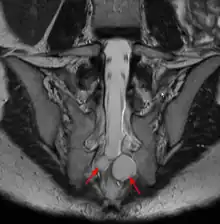

Un kyste de Tarlov (KT) ou kyste périneural, est une dilatation locale de l'espace sous-arachnoïdien se formant au contact d'une racine nerveuse, le plus souvent sacrée, dans la zone de transition entre arachnoïde et périnèvre (membrane externe du nerf). Il est fréquent et le plus souvent asymptomatique, mais peut parfois causer des symptômes neurologiques : on parle alors de maladie de Tarlov.

Quel que soit le système de classification, la définition d'un kyste de Tarlov est histopathologique car elle nécessite la présence de fibres de racines nerveuses de la colonne vertébrale dans la paroi du kyste ou dans sa cavité. Les kystes de Tarlov sont définis comme des lésions sacciformes, remplies de LCS, situées dans l'espace extradural du canal spinal sacré et formées à l'intérieur de la gaine de la racine nerveuse au ganglion de la racine dorsale.